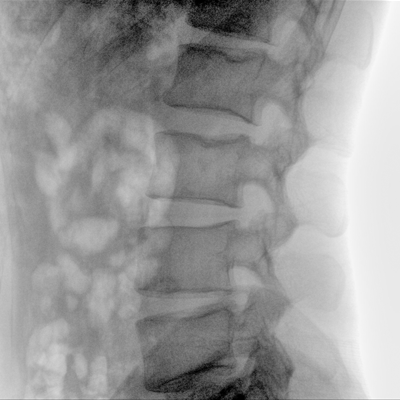

骨科: 經(jīng)皮錐體成形術(shù)、經(jīng)皮椎間盤臭氧治療術(shù)、胸脊椎固定、骨活檢、腰椎內(nèi)固定術(shù)等。

優(yōu)質(zhì)平板探測(cè)器、可靈活升降調(diào)節(jié)SID、獨(dú)特圖像處理系統(tǒng)、高品質(zhì)濾線柵,大視野成像清晰不失真。

采用智能劑量控制技術(shù),可根據(jù)不同體型和不同部位,準(zhǔn)確調(diào)節(jié)投照劑量。使操作者在任何使用環(huán)境下,都能實(shí)現(xiàn)低劑量、診視圖像清晰的效果。